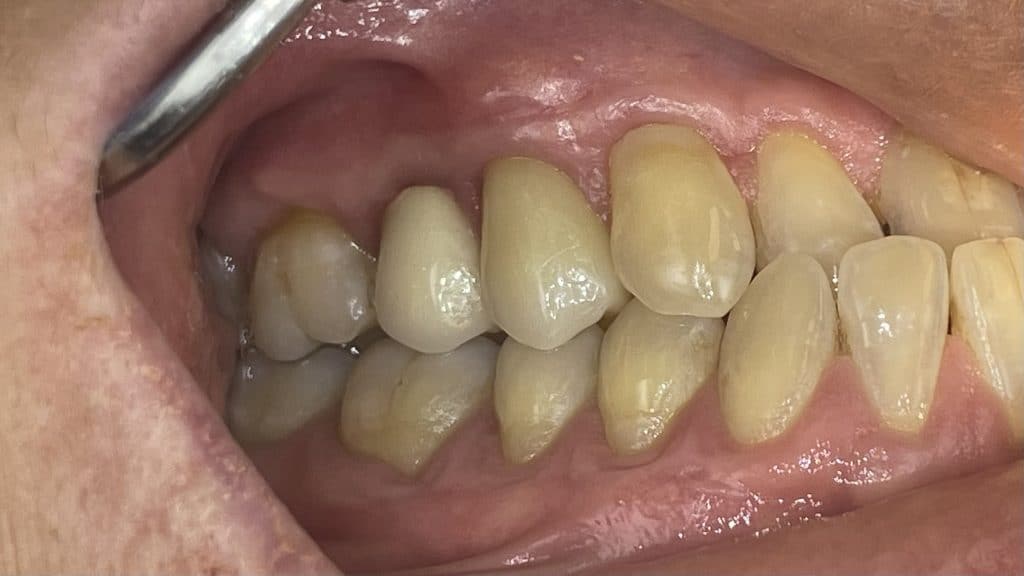

pre operative photo 1° quadrant

temporary crown of 1.4